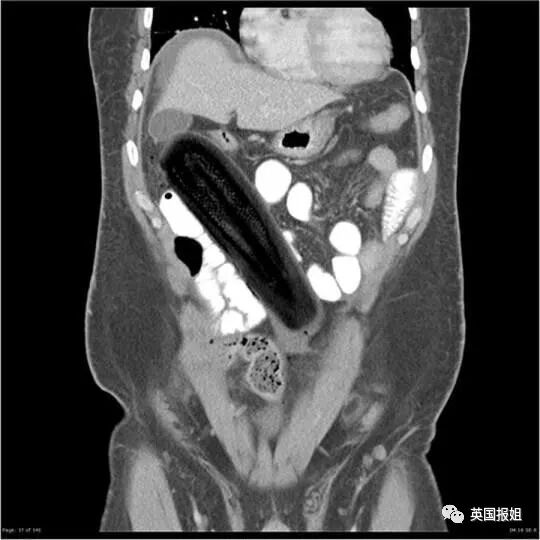

▷西葫芦

在一位50岁男性的腹腔内,可以看到这颗19厘米长的蔬菜,顶端紧挨着胆囊。

研究这个案例的医生们发出了讨论:

到底是使了多大劲儿,才能用一个圆钝的蔬菜怼到直肠穿孔。